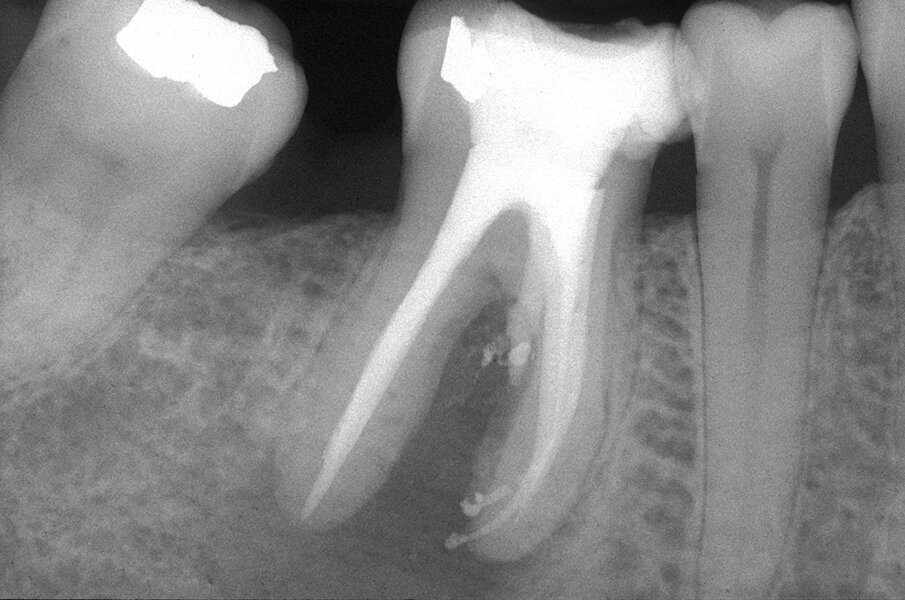

Queste perforazioni possono avvenire nel corso della strumentazione di canali curvi, per l’esecuzione del cosiddetto “trasporto esterno” del forame apicale. Una volta eseguita la perforazione, se l’operatore riesce a ritrovare e preparare il canale originale (con l’utilizzo di strumenti sottili e precurvati, molta irrigazione e soprattutto molta pazienza), il danno provocato dalla perforazione sarà minimo in quanto, soprattutto se la perforazione è piccola, si comporterà come un piccolo canale laterale che sarà facilmente otturato. Se invece il canale originale è rimasto intasato dai detriti di fango dentinale e gli strumenti ogni volta ripercorrono il cammino della perforazione, in tale caso il canale deve essere otturato con le metodiche tradizionali e successivamente l’apice contenente la porzione non trattata del canale radicolare deve essere rimosso per via chirurgica, soprattutto se stiamo trattando un dente necrotico o se siamo di fronte ad un ritrattamento (Figg. 1a-1e).